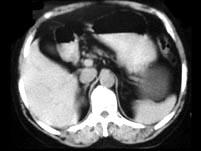

问题 女,55岁,发热,左侧腰部痛胀不适4天,CT检查如图所示,下列说法错误的是 ( )

选项 A、考虑为多囊肾合并感染 B、考虑为多发肾囊肿合并感染 C、病灶境界清晰,囊内密度近似水的密度 D、肾前筋膜增厚 E、左肾上极和下极各可见一个类圆形的囊性病灶

答案 A